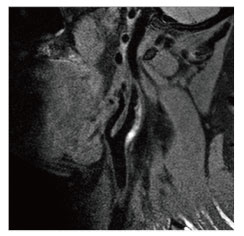

当院のMRI画像集